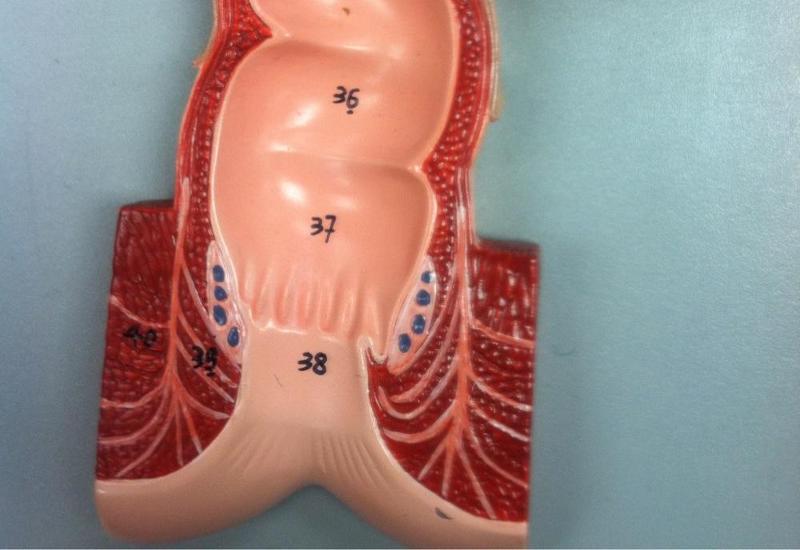

Anal Canal

38

Anus

Rectum